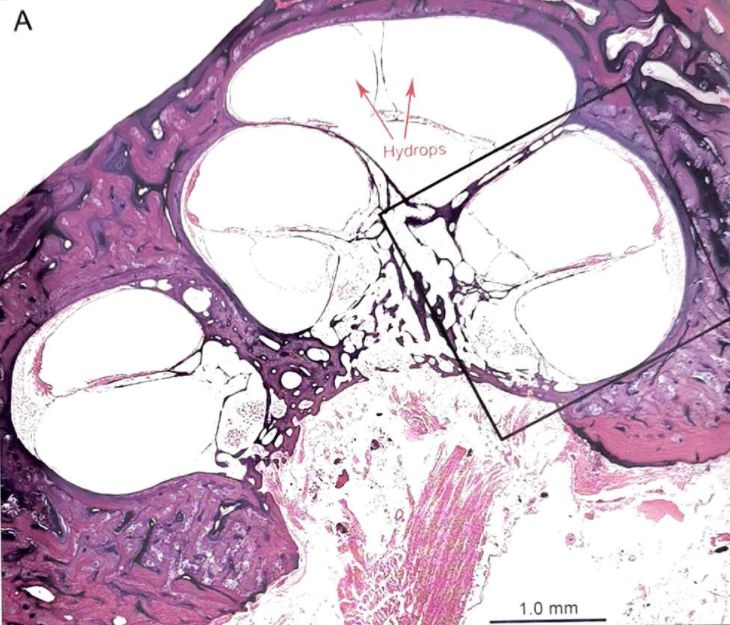

内淋巴积水(EH)自Hallpike和Yamakawa首次发现并报道以来,一直是颞骨组织病理学研究中非常常见的病理学发现。Paparella报道,MD最重要的组织病理学改变是耳蜗和球囊的内淋巴积水,即内耳的前下部分(图1)。从发育学来看,内耳的迷路膜在妊娠第6-12周发育,前下部分的结构比后上部分发育晚。而发育越晚的结构(耳蜗和球囊),可能越容易受到宫内损伤,从而导致MD的听觉症状发生率越高。

图1 右耳,耳蜗中段。中阶明显积水扩张